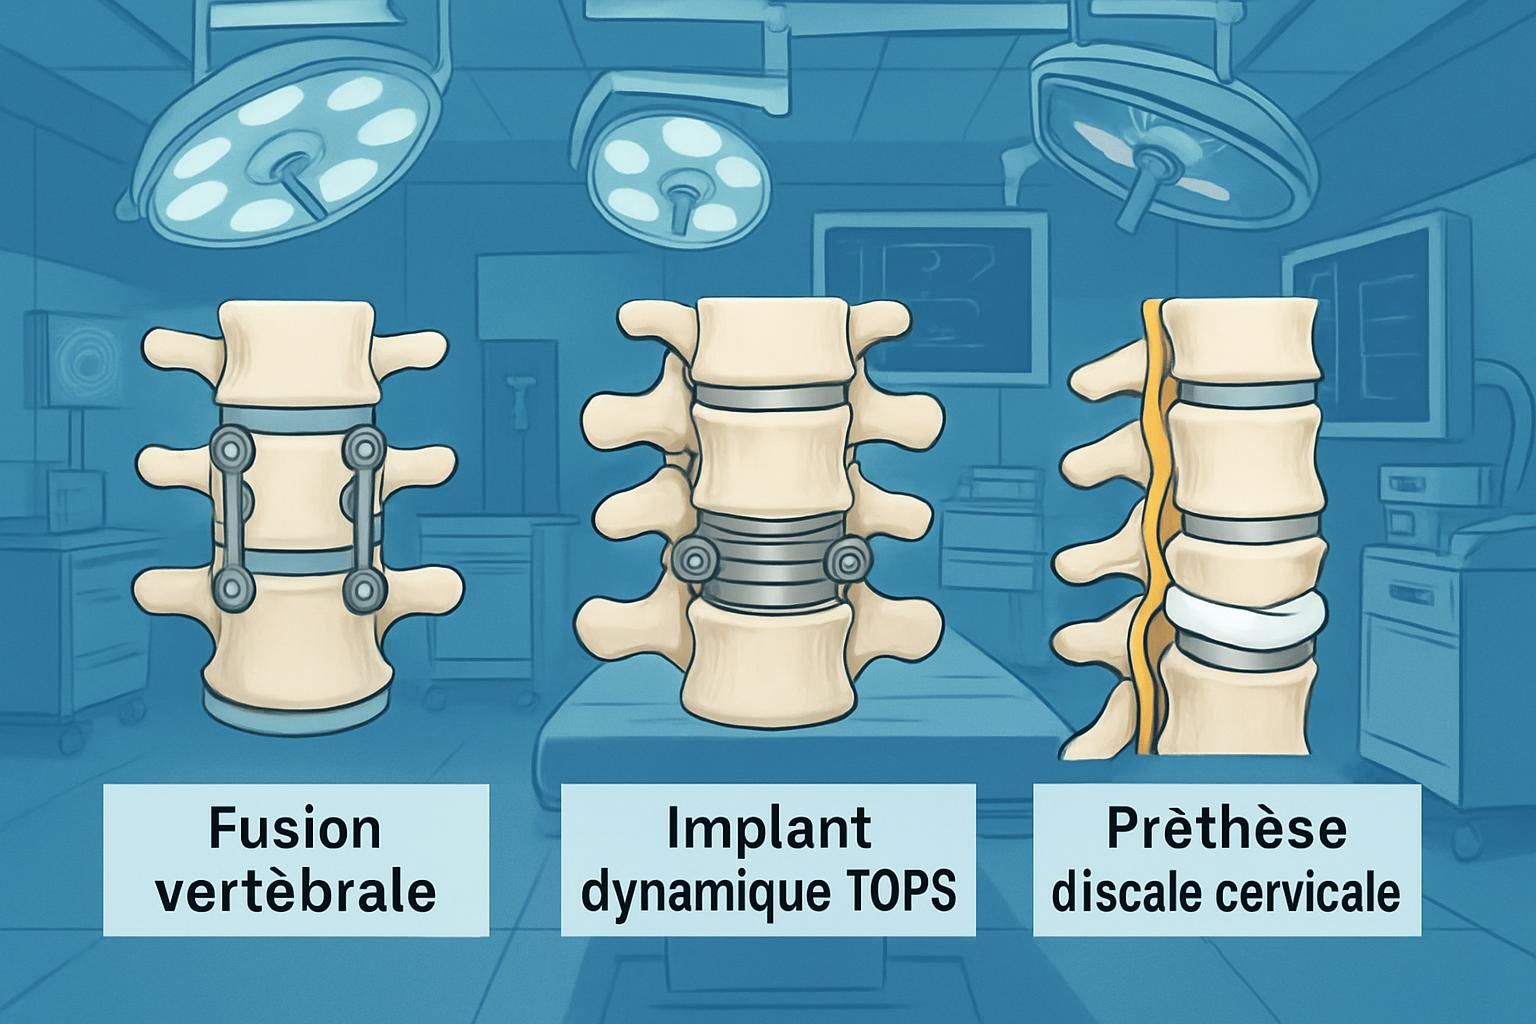

05/02/2026La chirurgie du rachis a longtemps reposé sur la fusion vertébrale, solution traditionnelle visant à stabiliser des segments osseux du dos afin de soulager la douleur et corriger des déformations. Cependant, cette approche rigide engendre souvent une perte significative de mobilité rachidienne, pouvant induire des complications à long terme telles que la dégénérescence des segments adjacents. Face à cette problématique, la recherche médicale et technologique a fait émerger des alternatives modernes et innovantes, notamment les implants dynamiques. Ces dispositifs offrent une préservation fonctionnelle remarquable, limitant ainsi la rigidité tout en garantissant une stabilité optimale. Le recours à ces solutions chirurgicales novatrices, largement disponibles en France et associées à un accompagnement personnalisé, permet aujourd’hui aux patients québécois d’envisager une prise en charge plus globale et efficace, à la fois sur le plan biomécanique et humain.

L’un des enjeux majeurs en chirurgie du rachis est de concilier stabilité et mobilité. La fusion vertébrale traditionnelle, bien qu’efficace sur le plan structural, bloque le mouvement entre les vertèbres fusionnées, ce qui peut augmenter la pression sur les segments vertébraux adjacents. Cette rigidité accentuée provoque souvent une usure prématurée, susceptible de générer des douleurs persistantes et nécessitant parfois des interventions complémentaires. Face à ce constat, des implants dits dynamiques ont été conçus pour offrir une alternative plus physiologique.

Parmi ces innovations, le système TOPS (Total Posterior Spine System) et l’implant IntraSPINE se distinguent par leur capacité à préserver le mouvement naturel tout en stabilisant la colonne vertébrale. Le système TOPS agit comme un stabilisateur postérieur intelligent qui contrôle les mouvements excessifs au niveau d’une vertèbre tout en permettant une certaine flexion, extension et rotation. L’implant IntraSPINE, quant à lui, est positionné dans l’espace interépineux pour soutenir la colonne et réduire la charge sur les disques vertébraux, favorisant ainsi une protection durable du rachis.

Malgré les avancées spectaculaires des implants dynamiques, la fusion vertébrale reste une solution éprouvée dans certains cas, notamment lorsque la stabilité absolue est impérative, comme en cas d’instabilité sévère ou de déformation majeure. Il importe d’évaluer chaque situation de façon personnalisée, en tenant compte des symptômes du patient, du degré de dégénérescence des disques, et des objectifs fonctionnels visés.

Le choix entre fusion, stabilisation dynamique ou même discoprothèse cervicale doit s’appuyer sur un dialogue approfondi avec les spécialistes et un bilan complet. La discoprothèse, par exemple, est une autre alternative particulièrement intéressante au niveau cervical, en restaurannt le mouvement physiologique tout en traitant la pathologie discale. Ces options sont décrites en détail avec leurs indications spécifiques afin d’aider les patients à comprendre les enjeux, notamment sur des plateformes expertes telles que prothèse discale cervicale alternatives.